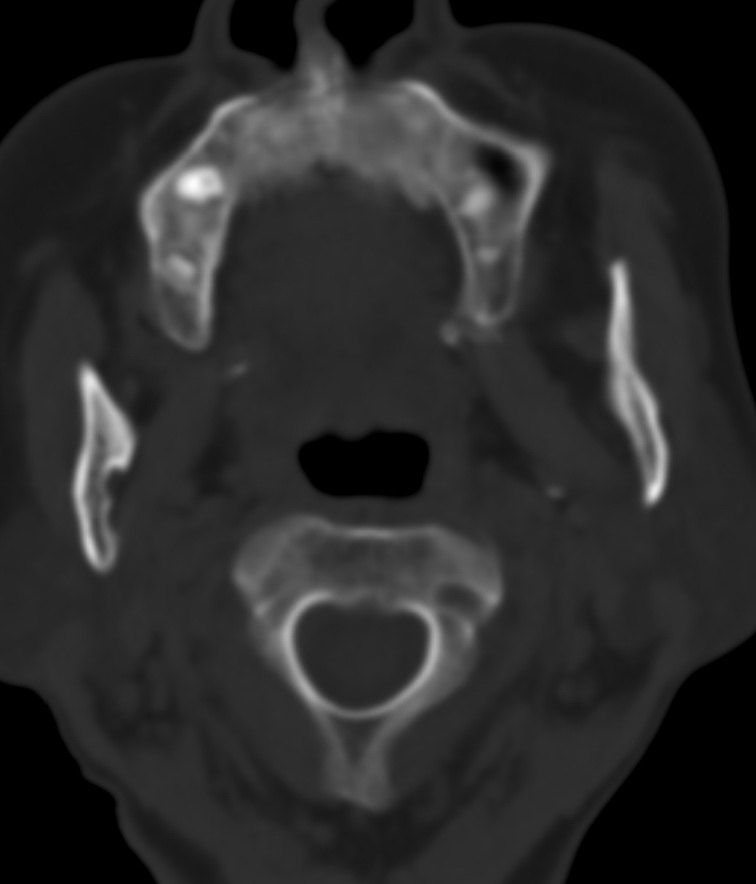

女,68岁。发现上唇无痛性肿块2年多,查体局部皮肤隆起,其余未见异常。

病灶ct值约42hu。

病理结果:唾液腺混合瘤。